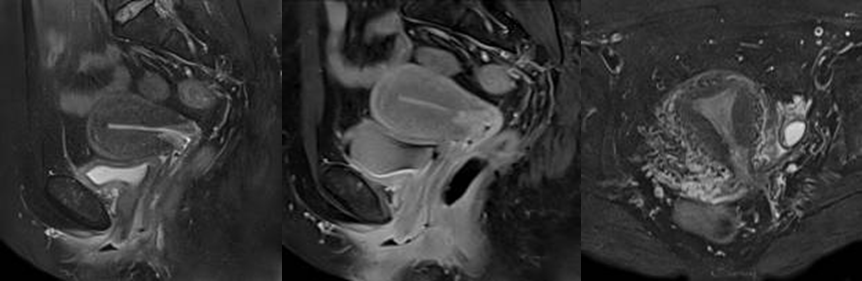

骨盤(子宮・卵巣)MRI

骨盤腔内の婦人科疾患(子宮がん、子宮内膜症、子宮筋腫、卵巣腫瘍etc)など女性特有の臓器の異常を放射線を使わずに検出します。女性の体が発する特有な症状(強い月経痛や月経過多、持続する下腹部の違和感、不正出血etc)など、婦人科トラブルのある方にお勧めしています。特に気になる症状がなくても、定期的な検診で病気を早期発見することも大切です。必要に応じて近隣の専門医にご紹介もできます。